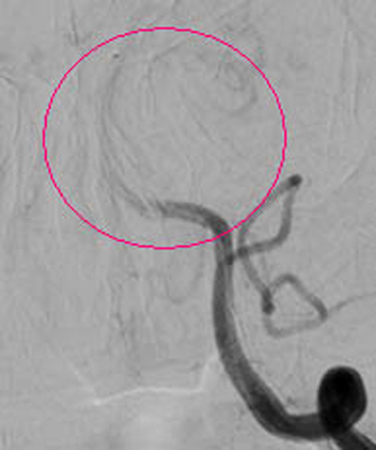

红圈内所示为经动脉接触溶栓后,血管再通。

患者张大妈,今年77岁,因“晨起洗脸时突发昏迷1个小时”急诊送入我院,行头颅CT示:排除脑出血、脑梗塞可能。神经外一科9:40接急诊内科紧急会诊通知,王和平医生9:45赶到急诊内科,在了解了病人的一般情况后,考虑患者来院比较及时,还在动脉溶栓时间窗内,遂急诊介入行全脑血管造影,明确为基底动脉完全闭塞(此病致死率高达90%),继而予尿激酶行基底动脉内接触溶栓!之后行造影明确,基底动脉通畅、显影(造影图片见后)!当天下午,患者神志基本清醒,竟然向医生提出要求:要求回家给儿孙做饭。